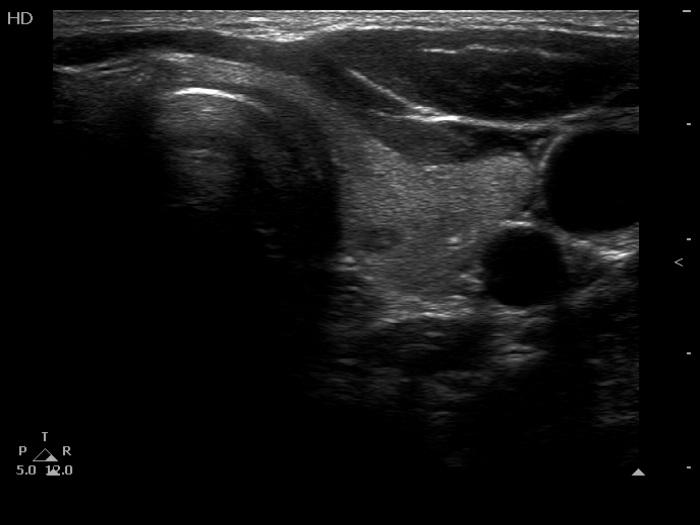

The composition of the nodule - case 1511 (ultrasonographic picture 8)

Right lobe, longitudinal scan